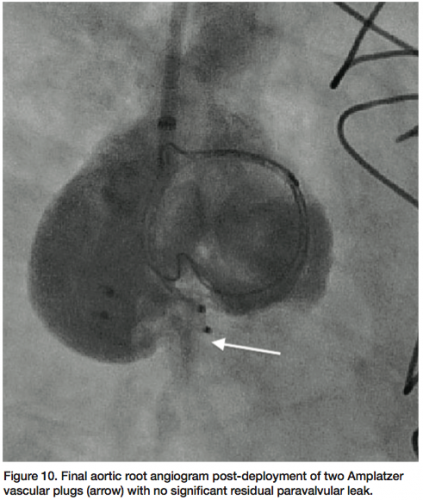

The patient underwent general anesthesia and endotracheal intubation for TEE evaluation in the cardiac catheterization laboratory. The paravalvular leak was crossed using a 6 French multipurpose diagnostic catheter and angled Glidewire, followed by a 6 French shuttle sheath (Cook Medical) over an Amplatz stiff wire (Figure 7). Using TEE and fluoroscopy, an 8 mm Amplatzer vascular plug II (AGA Medical) was deployed successfully, with persistent moderate regurgitation from the anteromedial region of the paravalvular aortic leak (Figure 8). The defect was

recrossed with a 5 French EBU guide catheter (Medtronic), followed by placement of a second 8 mm Amplatzer vascular plug (Figure 9). Final angiography (Figure 10) and TEE (Figure 11) of the paravalvular leak after two adjacent vascular plugs demonstrated no significant residual paravalvular leak. All catheters and sheaths were removed, with hemostasis achieved using a vascular closure device. The patient was discharged home without complications the following day.